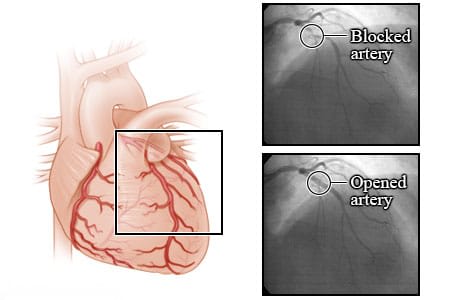

These X-rays show a blocked coronary artery before and after an angioplasty procedure. Before angioplasty, the blood flow is blocked by a narrowed artery. After the angioplasty, blood is flowing better through the newly opened artery. These X-rays are from an angiogram. An angiogram is a test that uses a special dye and camera to take X-ray pictures of the blood flow in an artery.